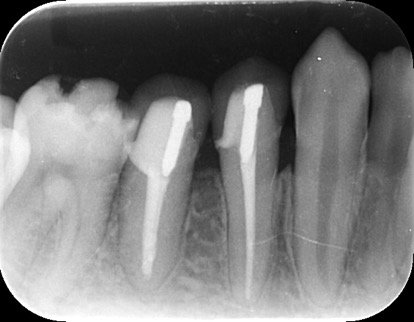

歯の根の治療は難しいことは先述しましたが、歯の内部からの治療だけでは治らないことがあります。

それは歯の先に枝分かれが多く存在し、そこにばい菌が入り込んで難治性となっているからです。ではその場合どうするのか?外科治療をします。その枝分かれの部分を切り落とすのです。今回はその前後のレントゲンの写真をお見せします。

| 根の中の薬が十分に充填されておらず、根の先が周りと比べて黒くなっており、炎症があると判断できます。 | 根の中にしっかりとお薬を緊密に充填しましたが、まだ根の先に黒くなっている部分があります。 |